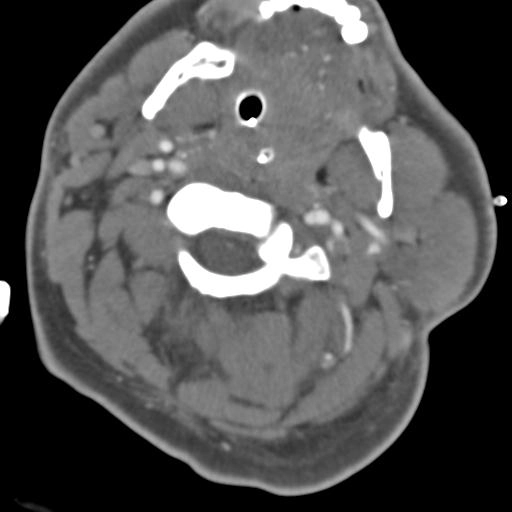

Tổn thương mạch máu não-cổ do chấn thương kín (Blunt Cerebrovascular Injury - BCVI)

Thang điểm Biffl phân loại tổn thương mạch máu não do chấn thương cùn (Blunt Cerebrovascular Injury - BCVI)